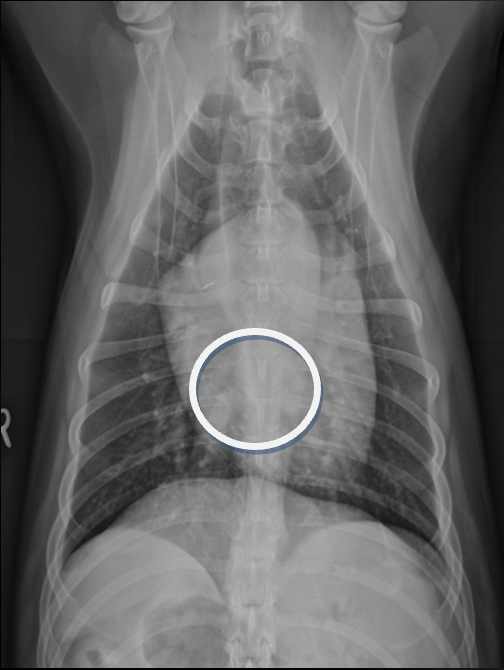

38

What is shown in this image?

left atrial enlargement